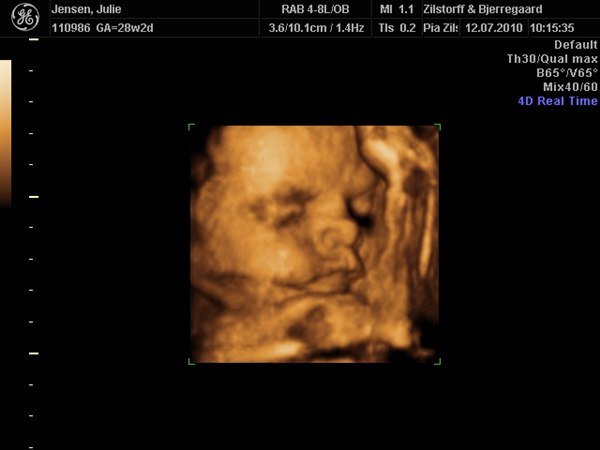

Hun skulle bestemt ikke snydes for noget så hun kiggede rigtig med da hun blev scannet og vinkede meget ivrigt til sin storebror som ikke kunne få øjne fra tvet og blev helt sat i putte mode da scanningsjordmoderen lod os høre hjertelyd hele 4 gange...

Kan slet ikke komme mig over hvor fantastisk det er at se det lille menneske inden i en

Vedhæftede fotos (klik for at se i fuld størrelse)